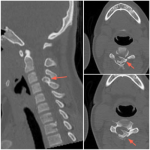

Osteocondroma cervical y mielopatía en niños: reporte de un caso y revisión de la bibliografía

Santiago Aguer, Javier Dal Lago, Matías L. Cullari, Facundo Aguirre, Eduardo Levy, Ruy Lloyd